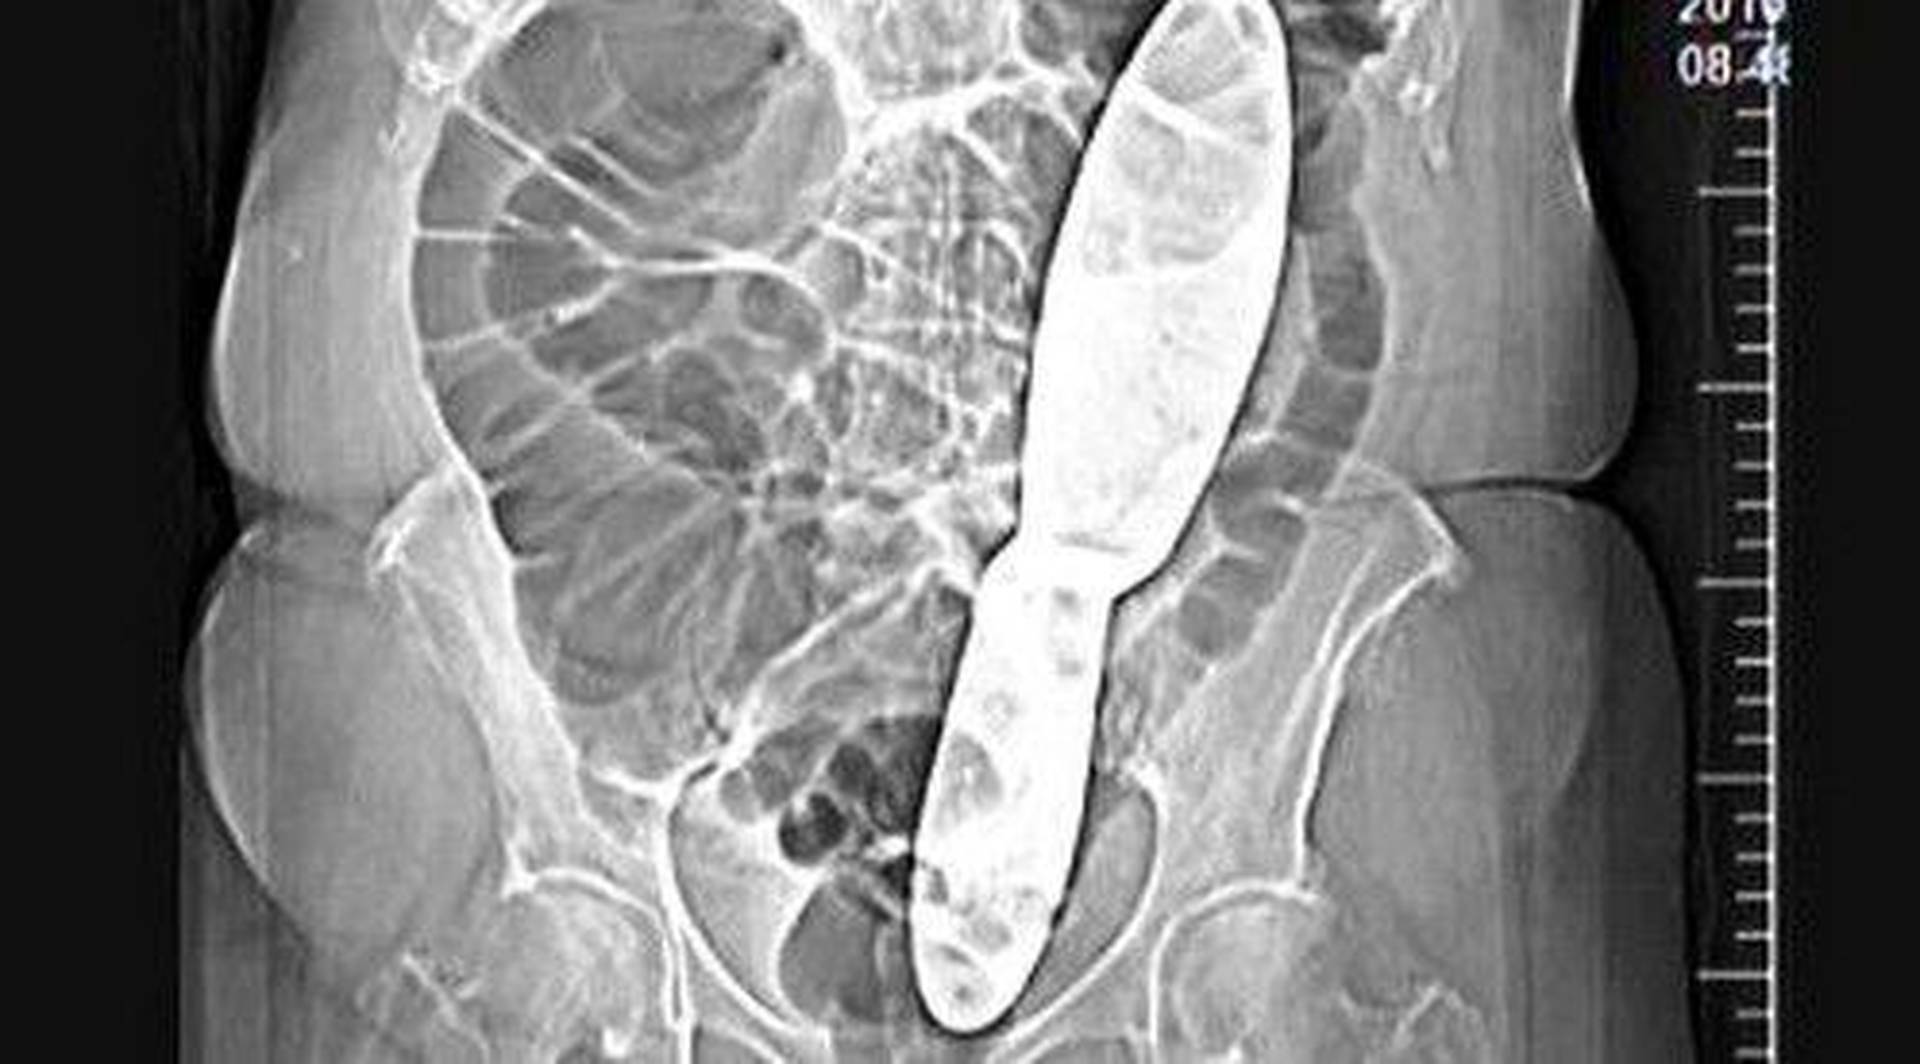

Удаление инородных тел из кишечника

Удаление инородных тел из кишечника 115 фотографий